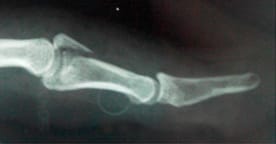

- Post-reduction the stability of the joint should be assessed and Elson's test5,6 performed to assess the central slip extensor mechanism. Any Boutonniere deformity which can be subtle should also be noted.

- In practice Elson's test is not always easy to perform or interpret. There is the traditional Elson's 5 and a modified version 6 which demonstrates the hyperextension of the DIPJ, as in in the left hand in (B).

- A Boutonnière deformity is the main concerning complication of a central slip tear/avulsion fracture

- The Boutonniere deformity sequence. (1) The PIP joint loses its dorsal extension force, so it starts to flex. (2) As the PIP flexes, the lateral bands slip volarly (below the axis of rotation of the PIP joint). (3) Once volar, the lateral bands act as flexors at the PIP joint rather than extensors—this locks in the deformity. Because the lateral bands are now tighter and pulled distally, they hyperextend the DIP joint. This results in flexion of the PIP joint with hyperextension of the DIP joint→ giving the characteristic “buttonhole” appearance — hence the name boutonnière (French for “buttonhole”).